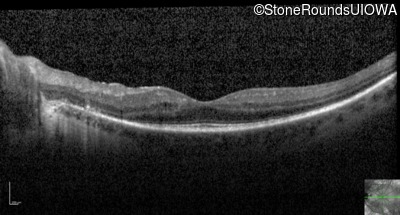

Optical Coherence Tomography - Left - 20/32

Exemplar / OCT Stack